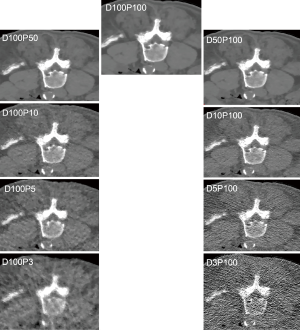

Tube current reduction was performed virtually. For this purpose, a simulation algorithm based on raw imaging data was used, which allowed for generating MDCT scans with virtually lowered tube currents (25-27). The original scan with full dose without dose reduction or sparse sampling was defined as D100P100. The corresponding simulations had 50% (D50P100), 10% (D10P100), 5% (D5P100), and 3% (D3P100) of the original X-ray tube current.

Sparse sampling and statistical iterative reconstruction (SIR)

Sparse sampling was simulated by reading only a reduced amount of projection angles and by deleting the remaining projections in the sonogram (27,28). Sparse-sampled images were generated as if MDCT was performed with only 50% (D100P50), 10% (D100P10), 5% (D100P5), and 3% (D100P3) of the original projection data.

Mean MD was 6.41±13.55 HU for the erector spinae muscles derived from original dose images (D100P100). Sparse sampling derived mean MD showed no significant changes (P=0.57) down to 5% of the original projections (D100P5). For the psoas muscle, mean MD amounted 39.86±6.14 HU. No significant changes in mean MD of the psoas muscle were observed down to D100P5 (P=0.22) (Table 2 and Figure 2). Representative images of virtually lowered tube current and sparse sampling are shown in Figure 2.